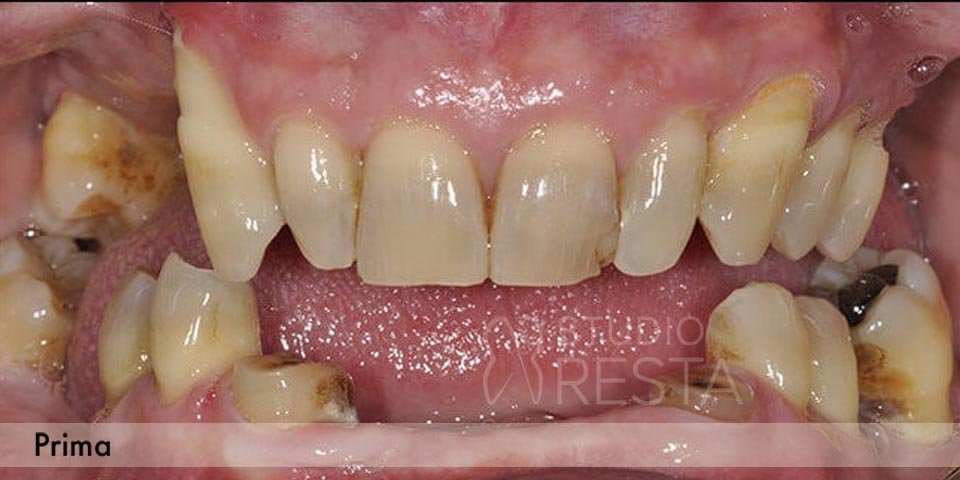

Alcuni casi clinici risolti con l'Implantologia (prima e dopo)

Vedrai le foto di decine di casi simili al tuo, brillantemente risolti